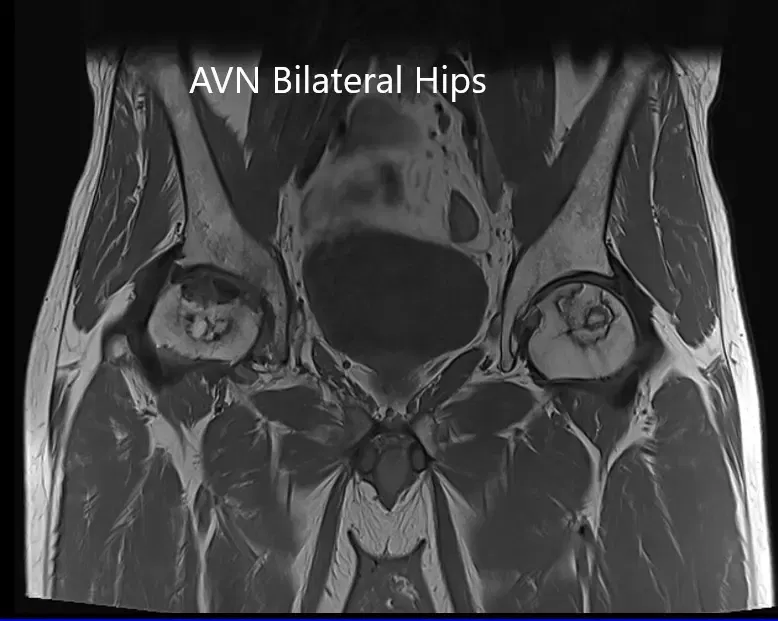

La resonancia magnética sugirió una marcada atenuación de señales en las cabezas femorales bilaterales. Hubo un colapso de la cabeza derecha y un precolapso en la etapa 2a de la cadera izquierda.

Resonancia magnética que muestra AVN bilateral de la cabeza femoral en T1WI

La resonancia magnética muestra un AVN bilateral femoral en T2WI